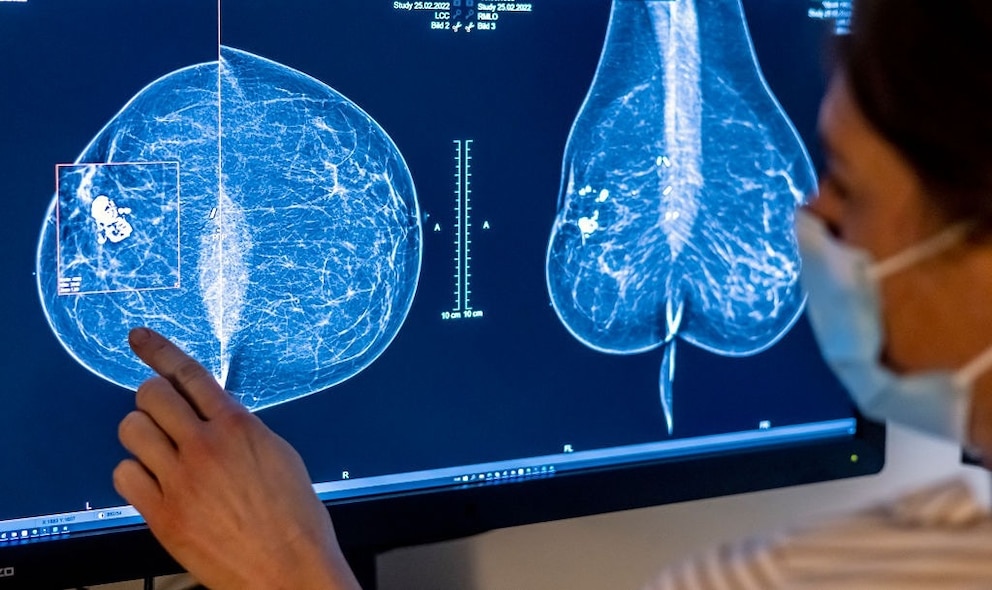

New 1-day surgery removes cancer and reconstructs the breast in the same operation

When the results of her routine mammogram came back with a diagnosis of stage 0 DCIS breast cancer in multiple areas of her right breast, Athaliah McPherson, a hairstylist and mom of one, said she wasn’t surprised.

McPherson’s diagnosis was not life-threatening in and of itself, but left unchecked, it might have developed into something more serious. Typically, doctors treat DCIS with partial or full breast removal surgery, sometimes followed by radiation or hormone therapy to lower future risk.